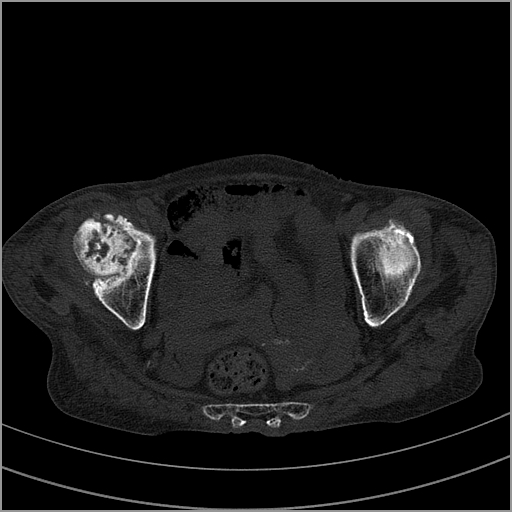

以下是引用老爱克斯新网客在2009-2-3 19:42:00的发言:[br]右侧髋臼及右侧股骨头可见明显骨质破坏,以溶骨性破坏为主,无明显硬化,髋关节间隙变窄,周围软组织明显肿胀,密度不均,脂肪间隙消失。[br] 诊断:右侧髋关节感染性病变,右侧髋关节结核的可能大。[br] 鉴别诊断:1.股骨头缺血坏死,单纯股骨头缺血坏死病例不会累积髋臼骨破坏。2。退行性关节炎,以骨质增生为主,伴有关节面硬化,骨质破坏呈多发小囊状破坏为主,其周围可见硬化环。3.股骨头缺血坏死晚期(第四期)骨质破坏可伴髋关节退行性变,可有骨质增生,但此时骨破坏以股骨头破坏为主,不应该伴有髋臼骨质破坏,因为股骨头的骨破坏是因血运中断,而没有髋臼的血运中断,又没有细菌的感染,怎么能造成髋臼的骨破坏呢。